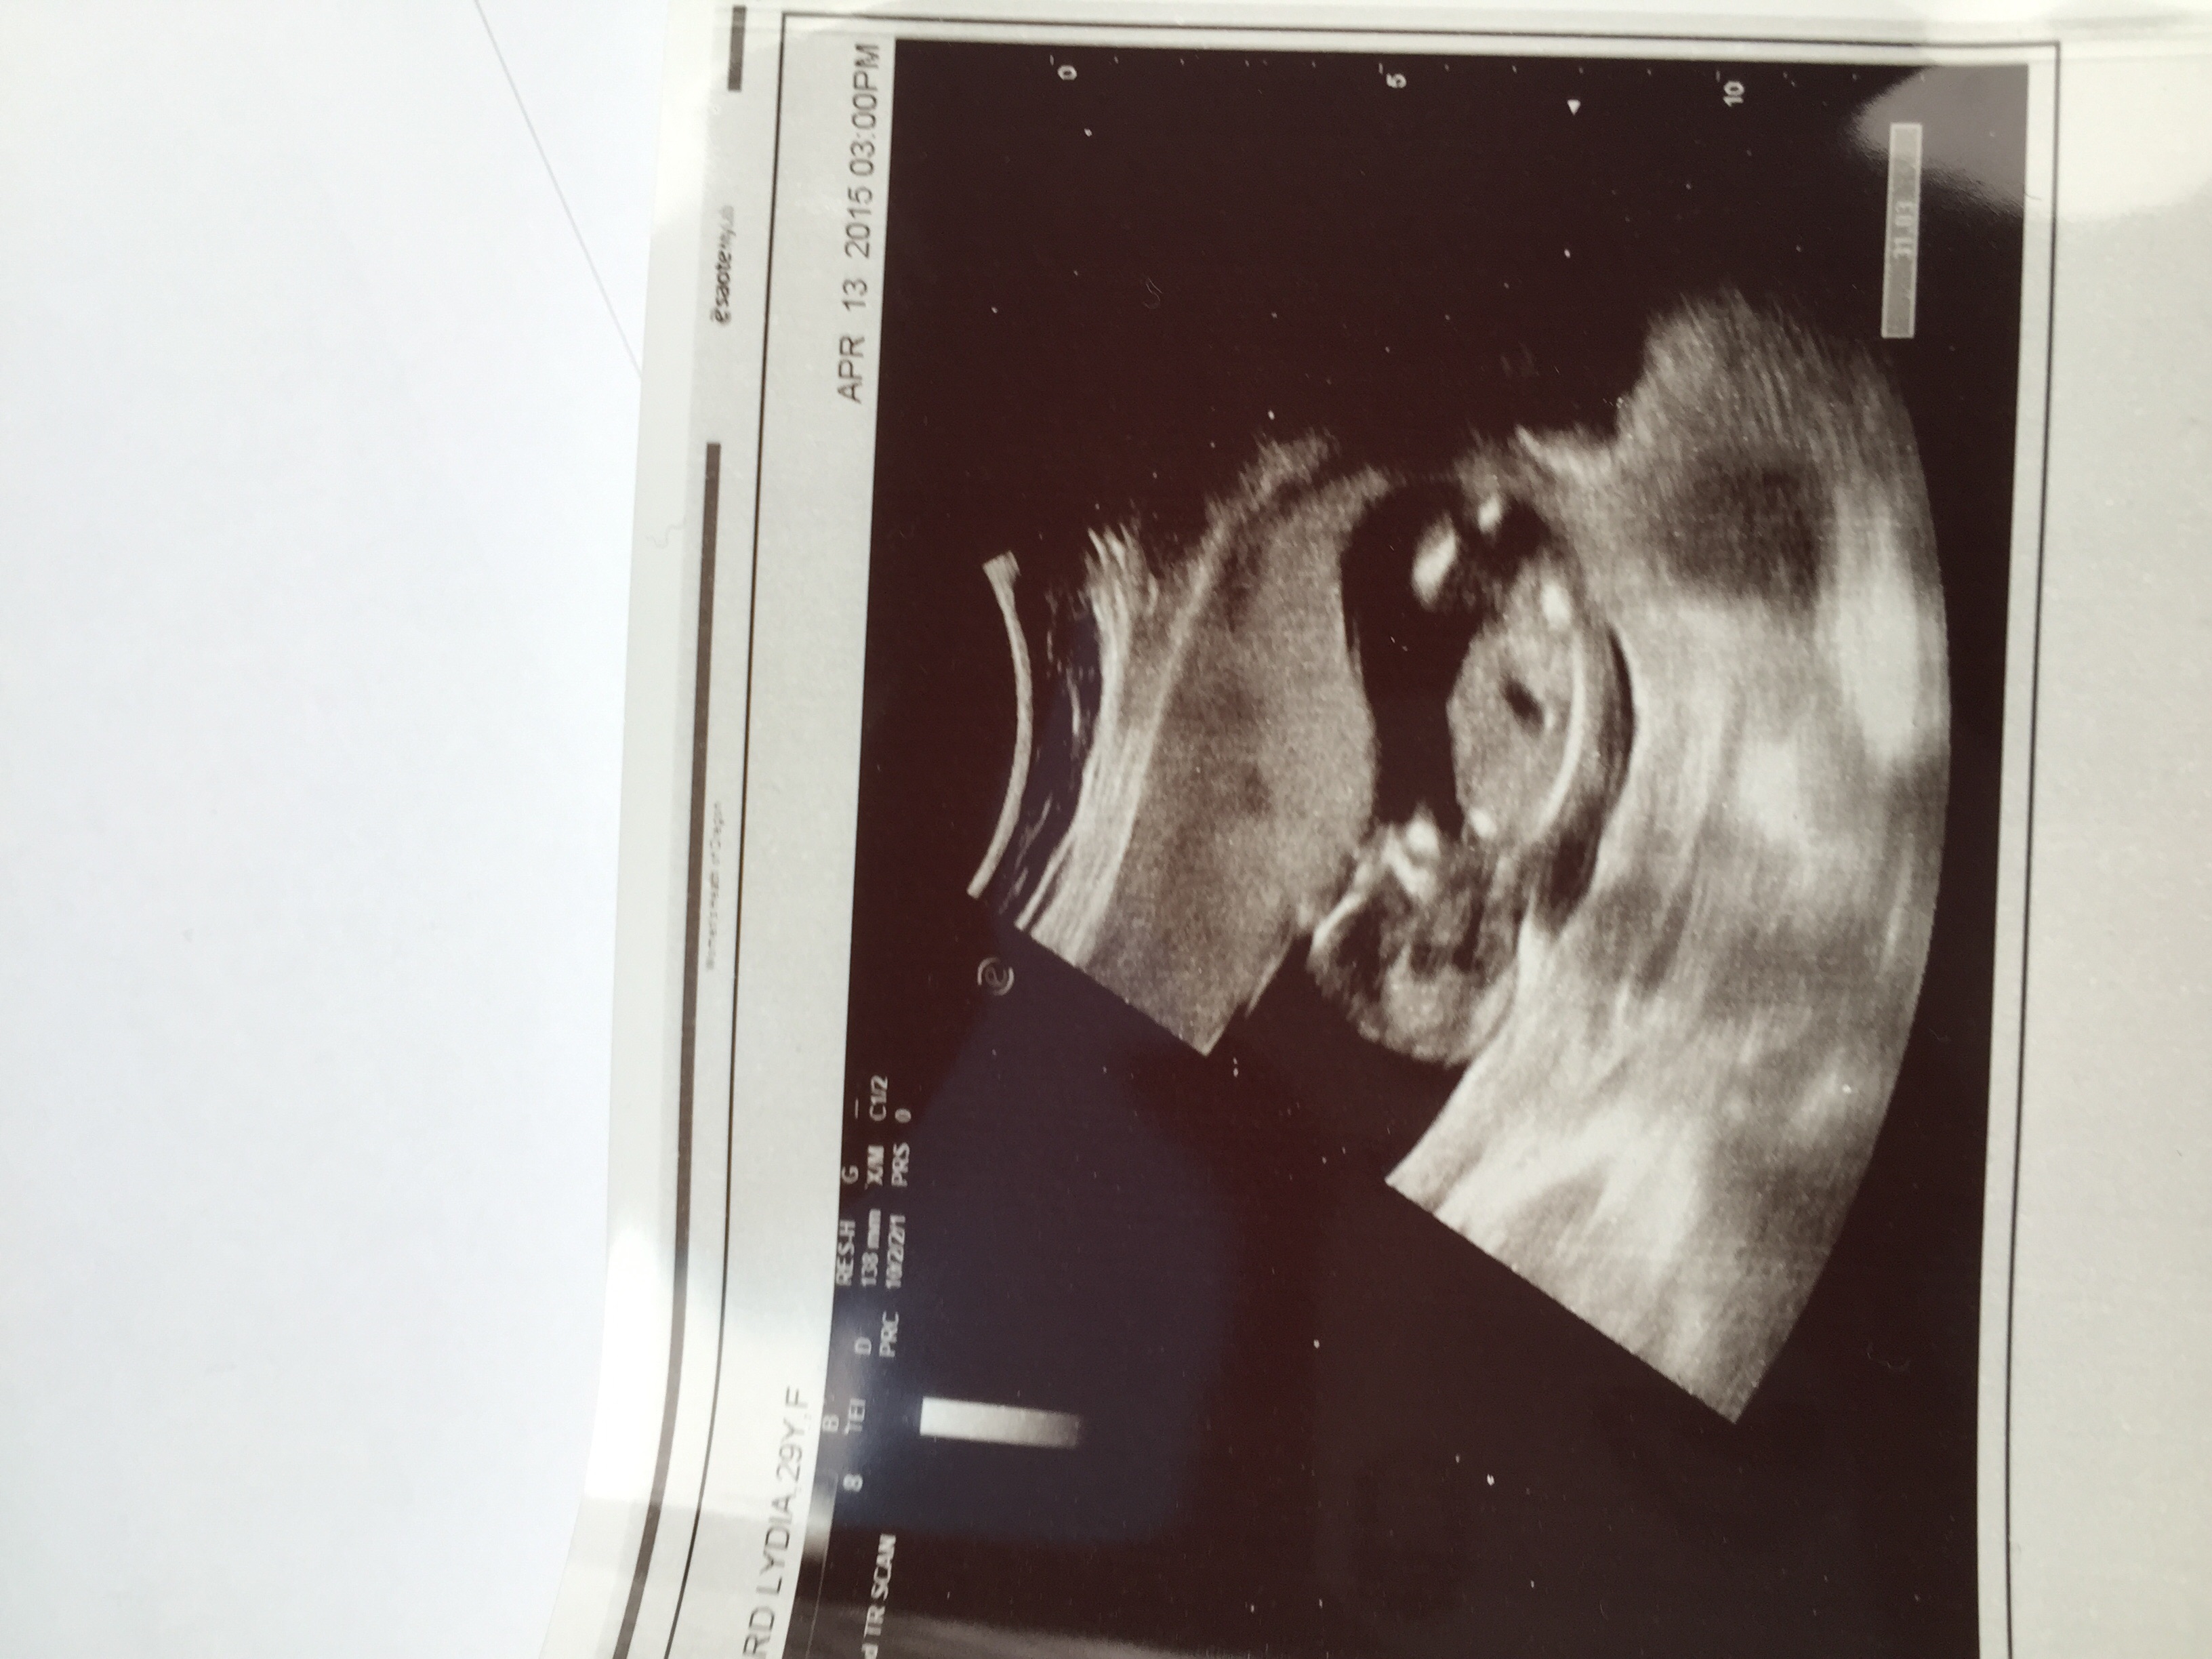

Got a surprise ultrasound today at 14w1d- thought we were just going to hear the heartbeat but we got pics too! Last time was at 9 weeks and she looked like a white smear on the U/S. Now look! So exciting!!